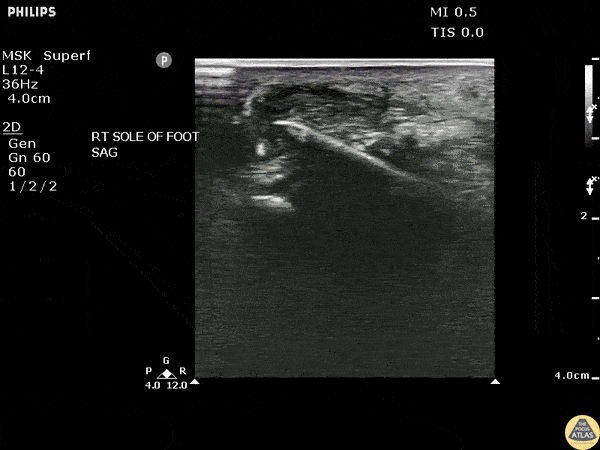

Soft Tissue - Toothpick Foreign Body

POCUS revealed a toothpick broken off in a patient’s heel in a long axis view. Image courtesy of Robert Jones DO, FACEP @RJonesSonoEM Director, Emergency Ultrasound; MetroHealth Medical Center; Professor, Case Western Reserve Medical School, Cleveland, OH View his original post here